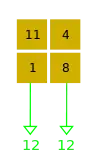

- A basic premise in back-projection is that any attenuation of the X-ray beam has occurred uniformly along the path followed from the source to the detector. Let's consider a simple tomographic slice containing just four voxels to illustrate the computational approach - see Figure 7.11. The first projection, P1 is obtained from a horizontal exposure from left to right in the figure. The back-projection of P1 involves putting the values 7 and 9 in both elements of the first and second rows, respectively. The second projection, P2 adds a 4 to the top right element, 1 to the bottom left element and 11 to the other two elements when it is back-projected. The other projections are treated in a similar fashion. Following regularisation of the data set the final image is obtained at the bottom left of the figure.